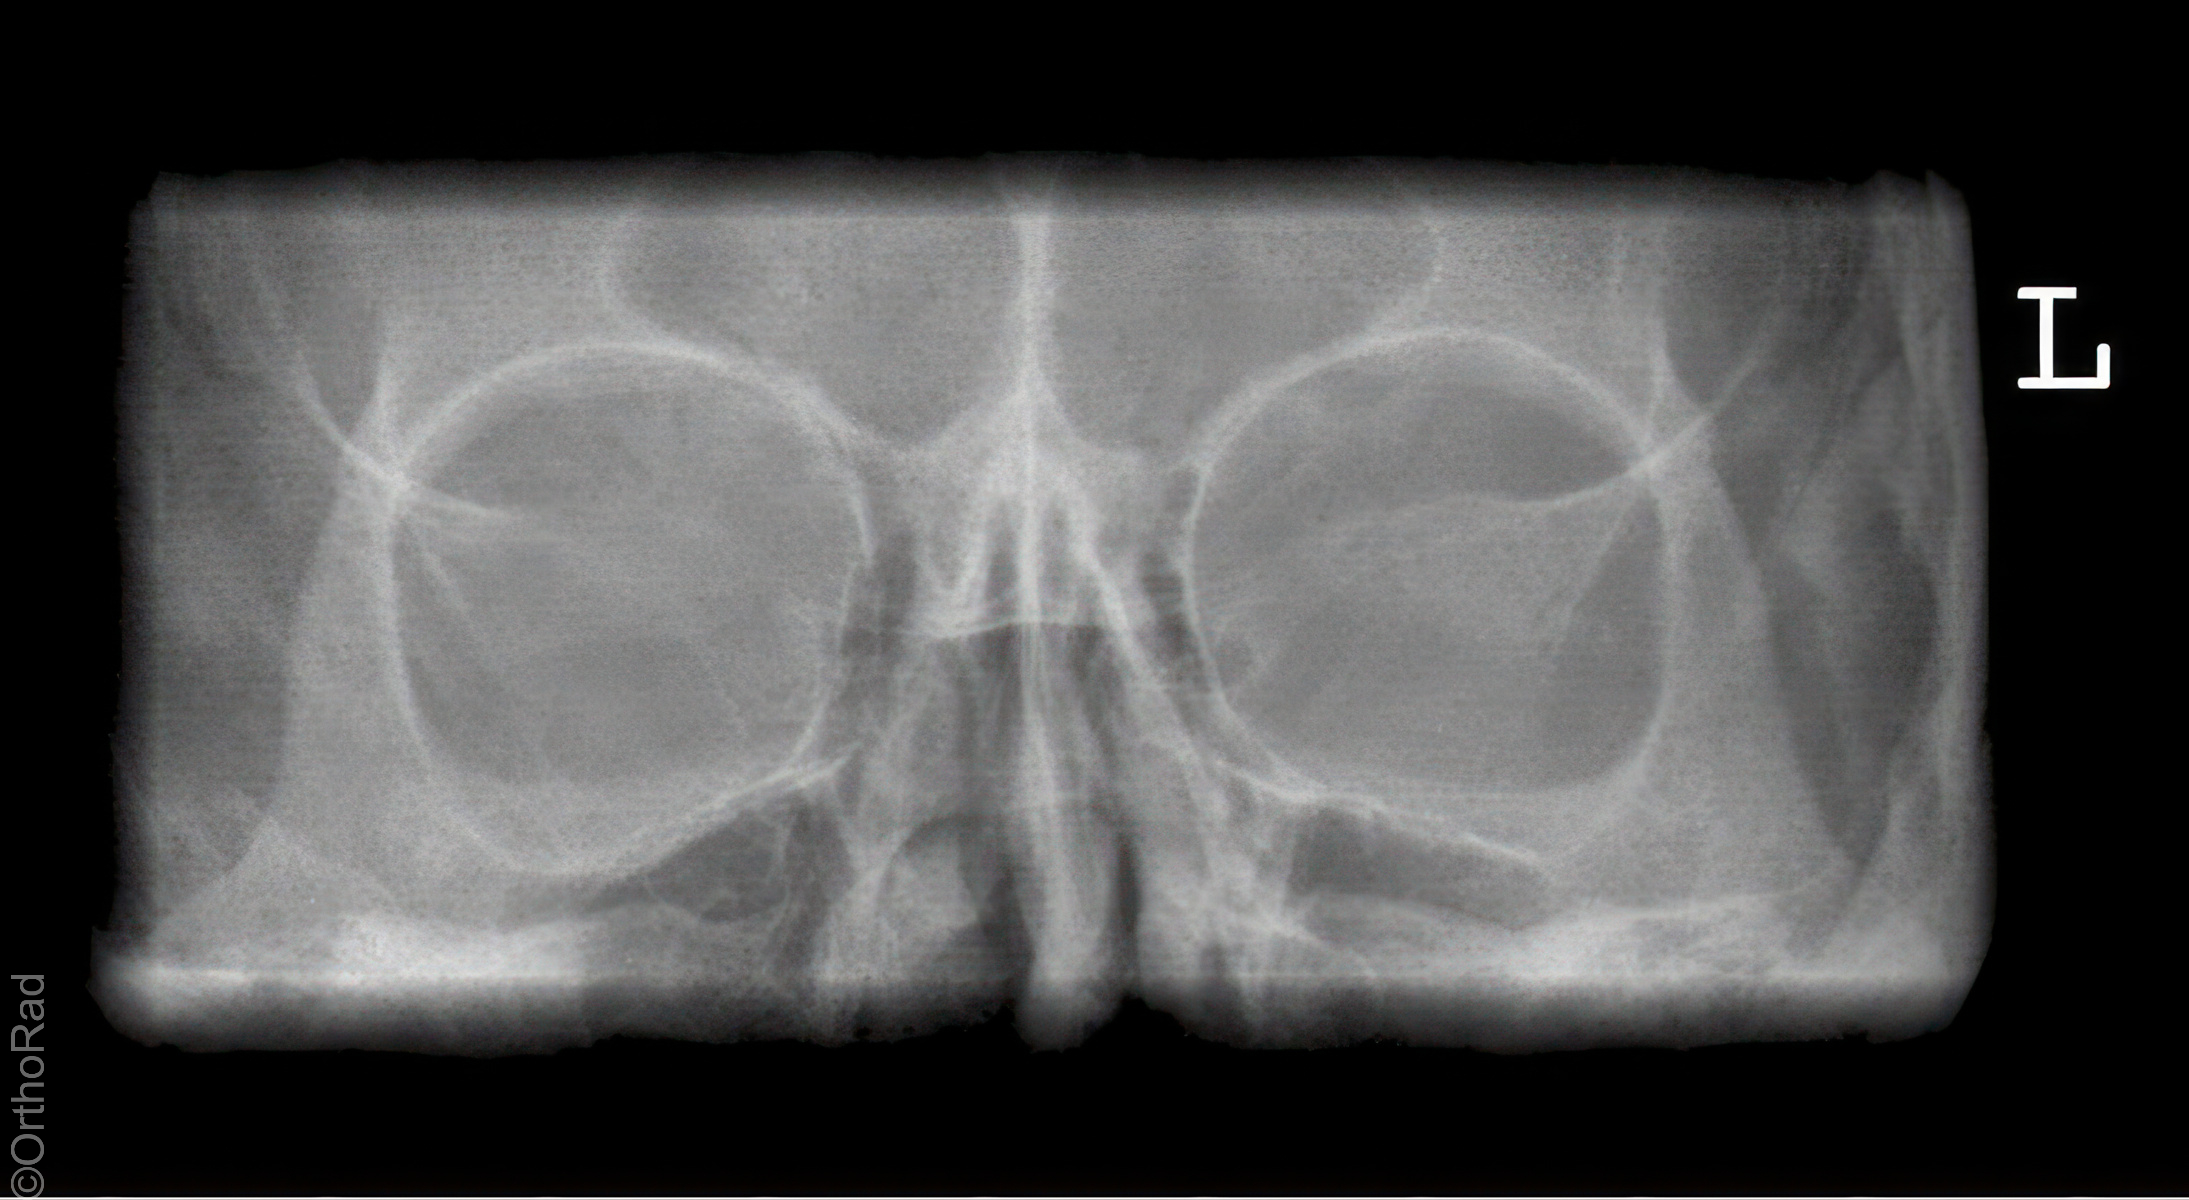

Nasennebenhöhlen (NNH)

Technik

• FDA: 1,15 m

• Ausgangsformat: Detektor oder 18/24 hoch

• mit Raster

Indikation

Sinusitis, Z. n. Osteosynthese

Lagerung

sitzend mit Gesicht zum Stativ

Hände festhaltend am Stativ

Rücken gerade

Mund weit geöffnet

Kinn liegt auf, Nase schwebt

Kopf anheben bis obere Zahnreihe und 1 QF über Ohr-Rand eine Linie bilden

Zentralstrahl

Querstrahl: 1 QF über oberen Ohrrand & Oberlippe

Längsstrahl: Medianebene

Einblendung

lateral auf Augenwinkel, cranial: auf Haaransatz

Anmerkung

Besonders auf symmetrische Lagerung achten. Im Sitzen ist evtl. Flüssigkeitsspiegel gut beurteilbar.

Qualitätskriterien

Symmetrische Darstellung des Gesichtsschädels: seitengleiche Distanz zwischen lateralem Rand der Augenhöhle und äußerer Schädelkontur. Die Pyramidenoberkanten kommen unmittelbar unterhalb des Kieferhöhlenbodens zum Liegen, also in die obere Zahnreihe, sodass die Kieferhöhlen überlagerungsfrei zur Darstellung kommen.